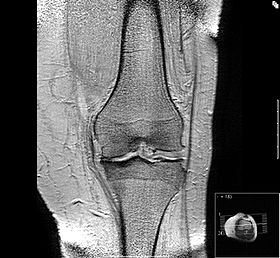

무릎 통증의 진단은 다음과 같은 방법으로 이루어집니다.

- 병력 청취 : 의사는 환자의 증상, 통증의 위치, 발생 시기, 그리고 과거의 부상 이력 등을 체크합니다.

- 신체검사 : 무릎의 움직임, 부기, 통증의 정도를 평가합니다.

- 영상 검사 : X-ray, MRI, CT 스캔 등을 통해 관절의 상태를 확인합니다. X-ray는 뼈의 구조를, MRI는 연조직의 손상을 평가하는 데 유용합니다.

- 혈액 검사 : 염증이나 감염의 징후를 확인합니다.

- 초음파 검사 : 연조직의 상태를 확인하는 데 유용하며, 특히, 부상이나 염증을 확인하는 데 도움을 줍니다.